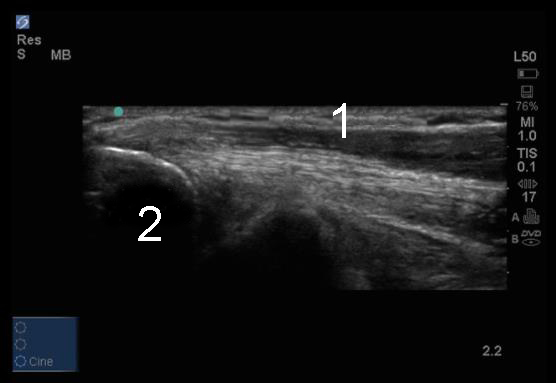

Elbow Common Flexor Tendons Image

Common Flexor Tendon

Lateral Epicondyle